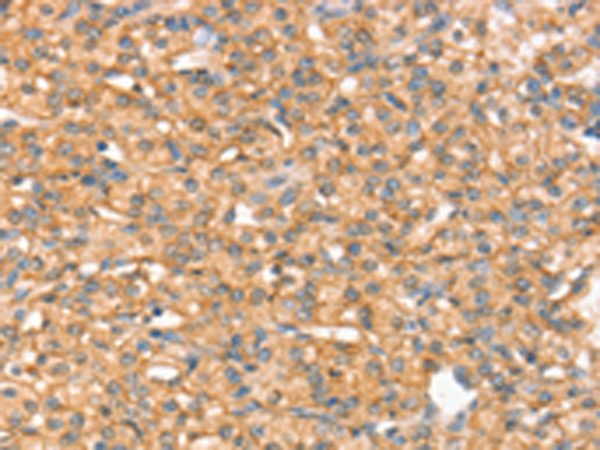

IHC positive control: |

Human prostate cancer |

IHC Recommend dilution: |

25-100 |